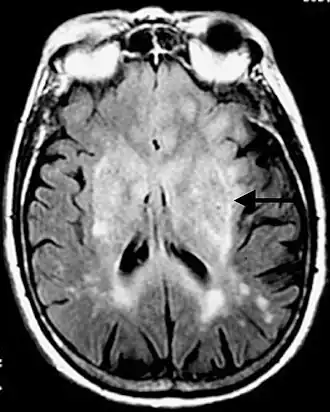

- Standardverfahren ist die Magnetresonanztomographie (MRT), auch Kernspintomographie genannt, ein diagnostisches Schnittbildverfahren zur Darstellung von Organen und Geweben mit Hilfe von Magnetfeldern. Sie basiert auf der Gewebestruktur und dem Wassergehalt und hat eine sehr hohe Erkennungsrate für Hirntumoren, ohne ionisierende Strahlung einzusetzen. Kontrastmittel ist nicht immer erforderlich. Die Magnetresonanzspektroskopie (MRS) ist ein in spezialisierten Zentren verfügbares Zusatzverfahren, um aus tumorverdächtigen Arealen ein Signalspektrum aufzunehmen und damit ihre chemische Zusammensetzung abzuschätzen.